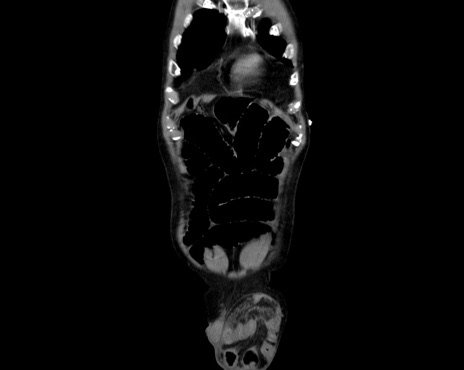

横断像

【症例】80歳代男性

【主訴】嘔吐

【現病歴】昨晩2回嘔吐あり、今朝になっても嘔吐あり。来院。

【既往歴】胃潰瘍

【身体所見】意識清明、BT 37.6℃、BP 166/95mmHg、HR 100bpm、SpO2 97%、腹部:平坦・軟、腸蠕動音聴取良好、圧痛なし。

【データ】WBC 21900、CRP 1.4